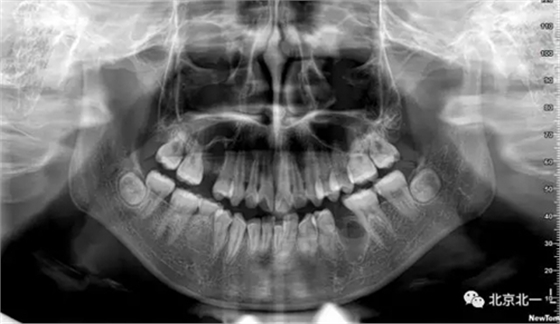

術(shù)后拍片